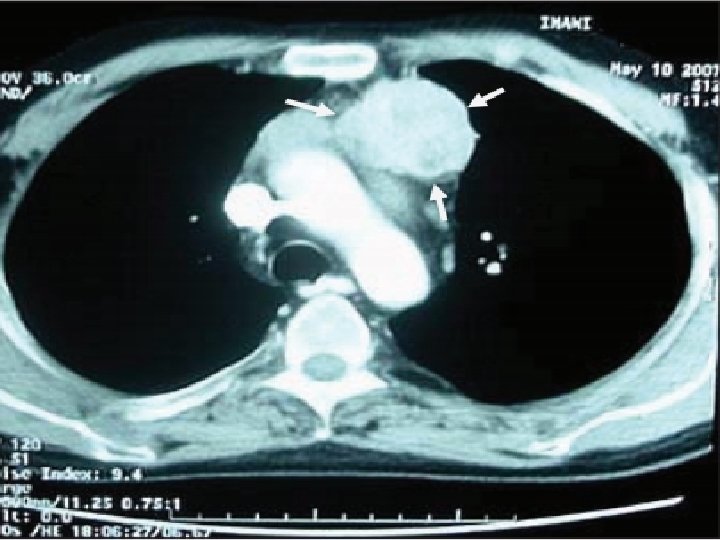

Ø A 53 Y. O lady was referred to us because of acromegalic features. Ø Her work up in another hospital revealed high IGF 1, and unsuppressed GH after glucose challenge. Ø Her pituitary MRI was interpreted as normal in 2 occasions. Ectopic acromegaly was highly suspected.

Ø Histopathologic evaluation revealed the mass is indeed a Paraganglioma. Ø IHC was positive for chromogranin

IHC showed positivity for GHRH.